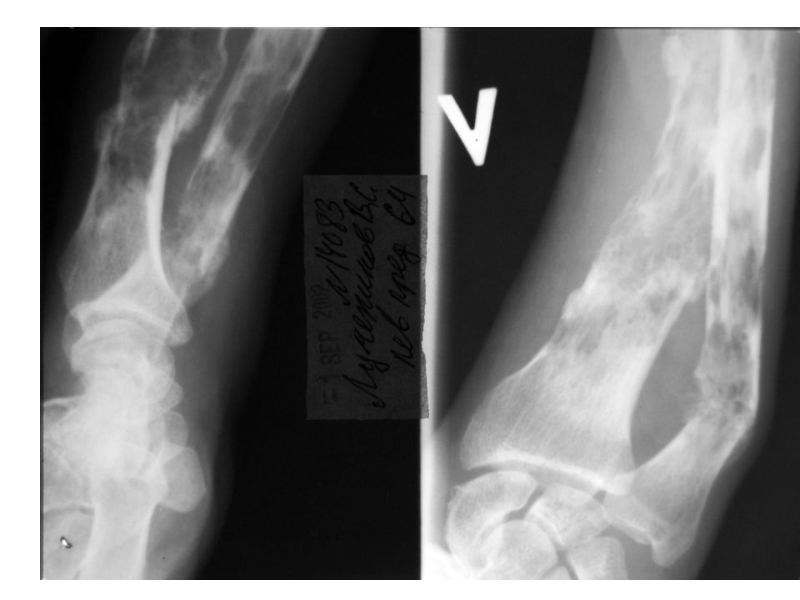

Слайд 25Клинические проявления ММ

Поражение костей

Множественные остеолитические очаги повреждения плоских костей

и эпифизов трубчатых костей

Диффузный остеопороз (остеопения)

Костные переломы

Уменьшение роста (вертебральный коллапс)

Болевой

синдром